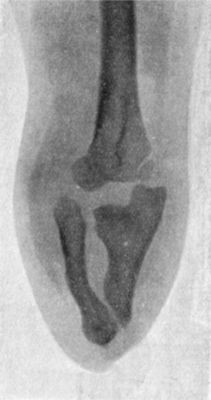

77 33.Radiogram of Supra-condylar Fracture of Humerus in a Child

81 34.Radiogram of T-shaped Fracture of Lower End of Humerus